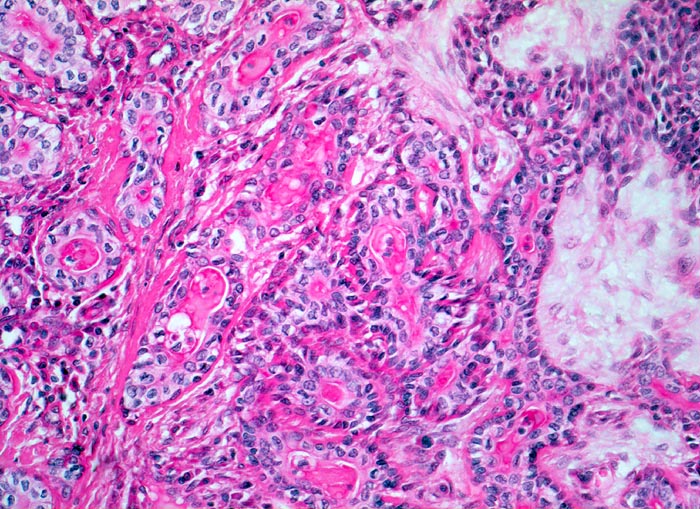

Die architektonischen und zytologischen Befunde sind äusserst variabel. Pleomorphe Adenome bestehen aus einer duktalen epithelialen, einer myoepithelialen und einer mesenchymalen Komponente mit myxoider, hyaliner, chondroider oder ossärer Differenzierung. Der Prozentuale Anteil der verschiedenen Komponenten ist von Tumor zu Tumor sehr unterschiedlich. Gangstrukturen werden von einem einreihigen duktalen Epithel ausgekleidet. Das Gangepithel kann eine Plattenepithelmetaplasie mit Verhornung zeigen. Die Myoepithelzellen umgeben die epithelial ausgekleideten Gangstrukturen, bilden Nester, solide Zellplatten, Trabekel oder liegen einzeln im mesenchymalen Stroma. Die Morphologie der Myoepithelien ist sehr variabel (spindelig, plasmazytoid, epitheloid, sternförmig oder basaloid).

• Scharf begrenzter bekapselter Tumor bestehend aus epithelialen, myoepithelialen und mesenchymalen Anteilen.

• Das Epithel bildet duktale Strukturen, welche von reichlich Myoepithelien umgeben werden.

• Epitheiale Gänge werden ausgekleidet von kubischen luminalen Zellen und einer oder mehreren äusseren Schichten myoepithelialer Zellen.

• In den stromareichen Arealen rechts finden sich plasmazytoide Myoepithelzellen mit reichlich eosinophilem Zytoplasma und einem exzentrisch gelegenen runden Kern.

• Die stromale Komponente ist teils mukoid, teils hyalinknorplig, teils hyalinisiert bindegewebig.